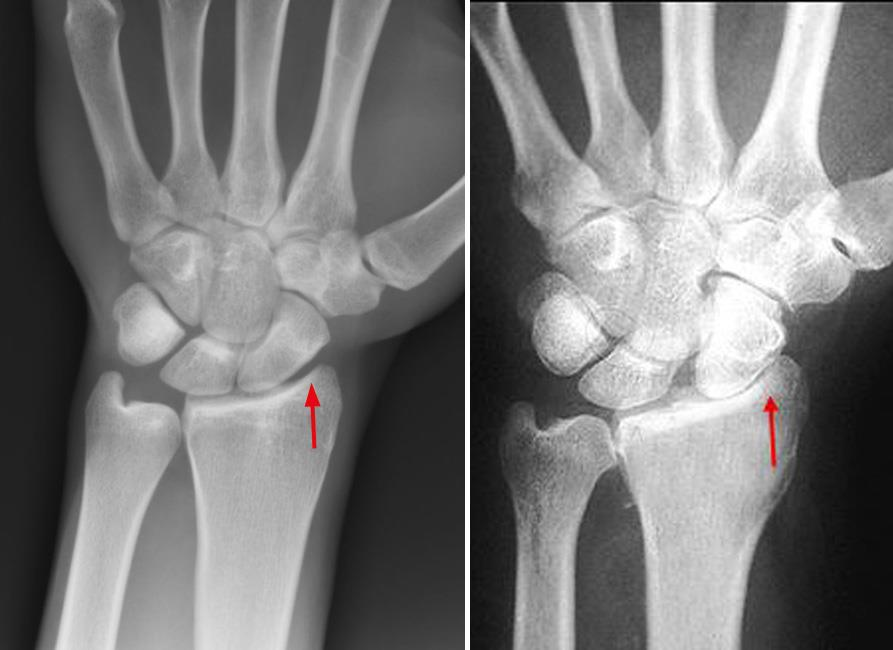

Wrist Scaphoid Fractures